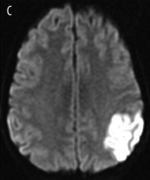

Diffusion Weighted Imaging (DWI)

- A method of measuring the Brownian motion of water molecules

- Diffusion within the intracellular fluid, diffusion within extracellular fluid, and between these areas will differ depending on pathology

- Ideal for cellular swelling especially in acute ischemic stroke which will be hyperintense